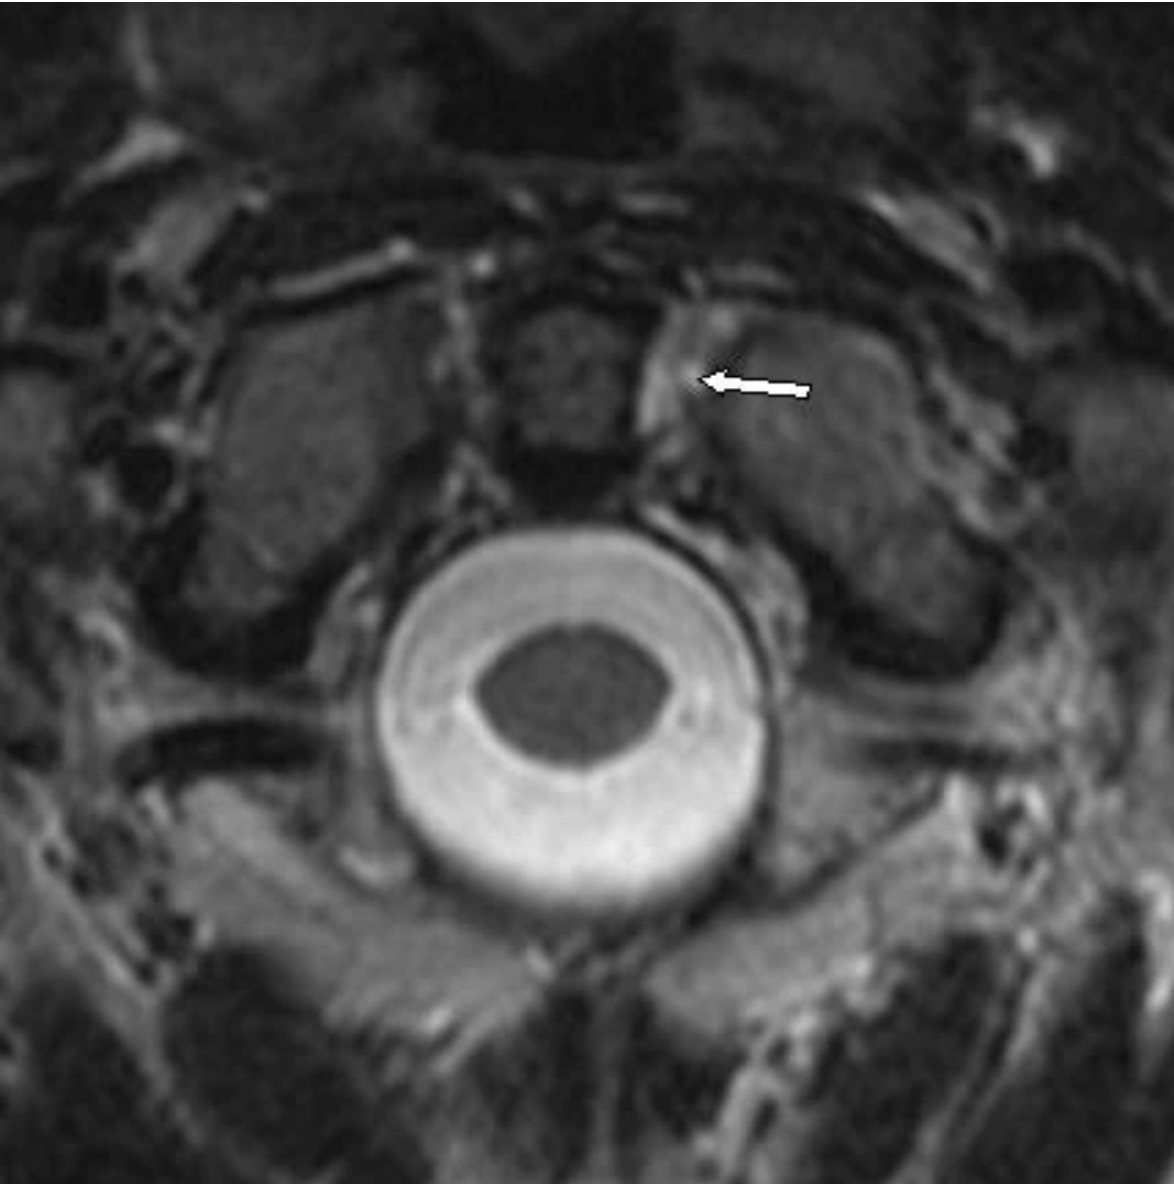

While the term chiropractic subluxation may be considered antiquated by some, to me, it remains a clinically meaningful concept. It can be applied to neuromusculoskeletal abnormalities that are definable, testable, and increasingly measurable through advanced biomarkers and modern diagnostic tools available today, that I discuss in my PostGradDC coursework, in an Clinical Pearl that I wrote and a past article.